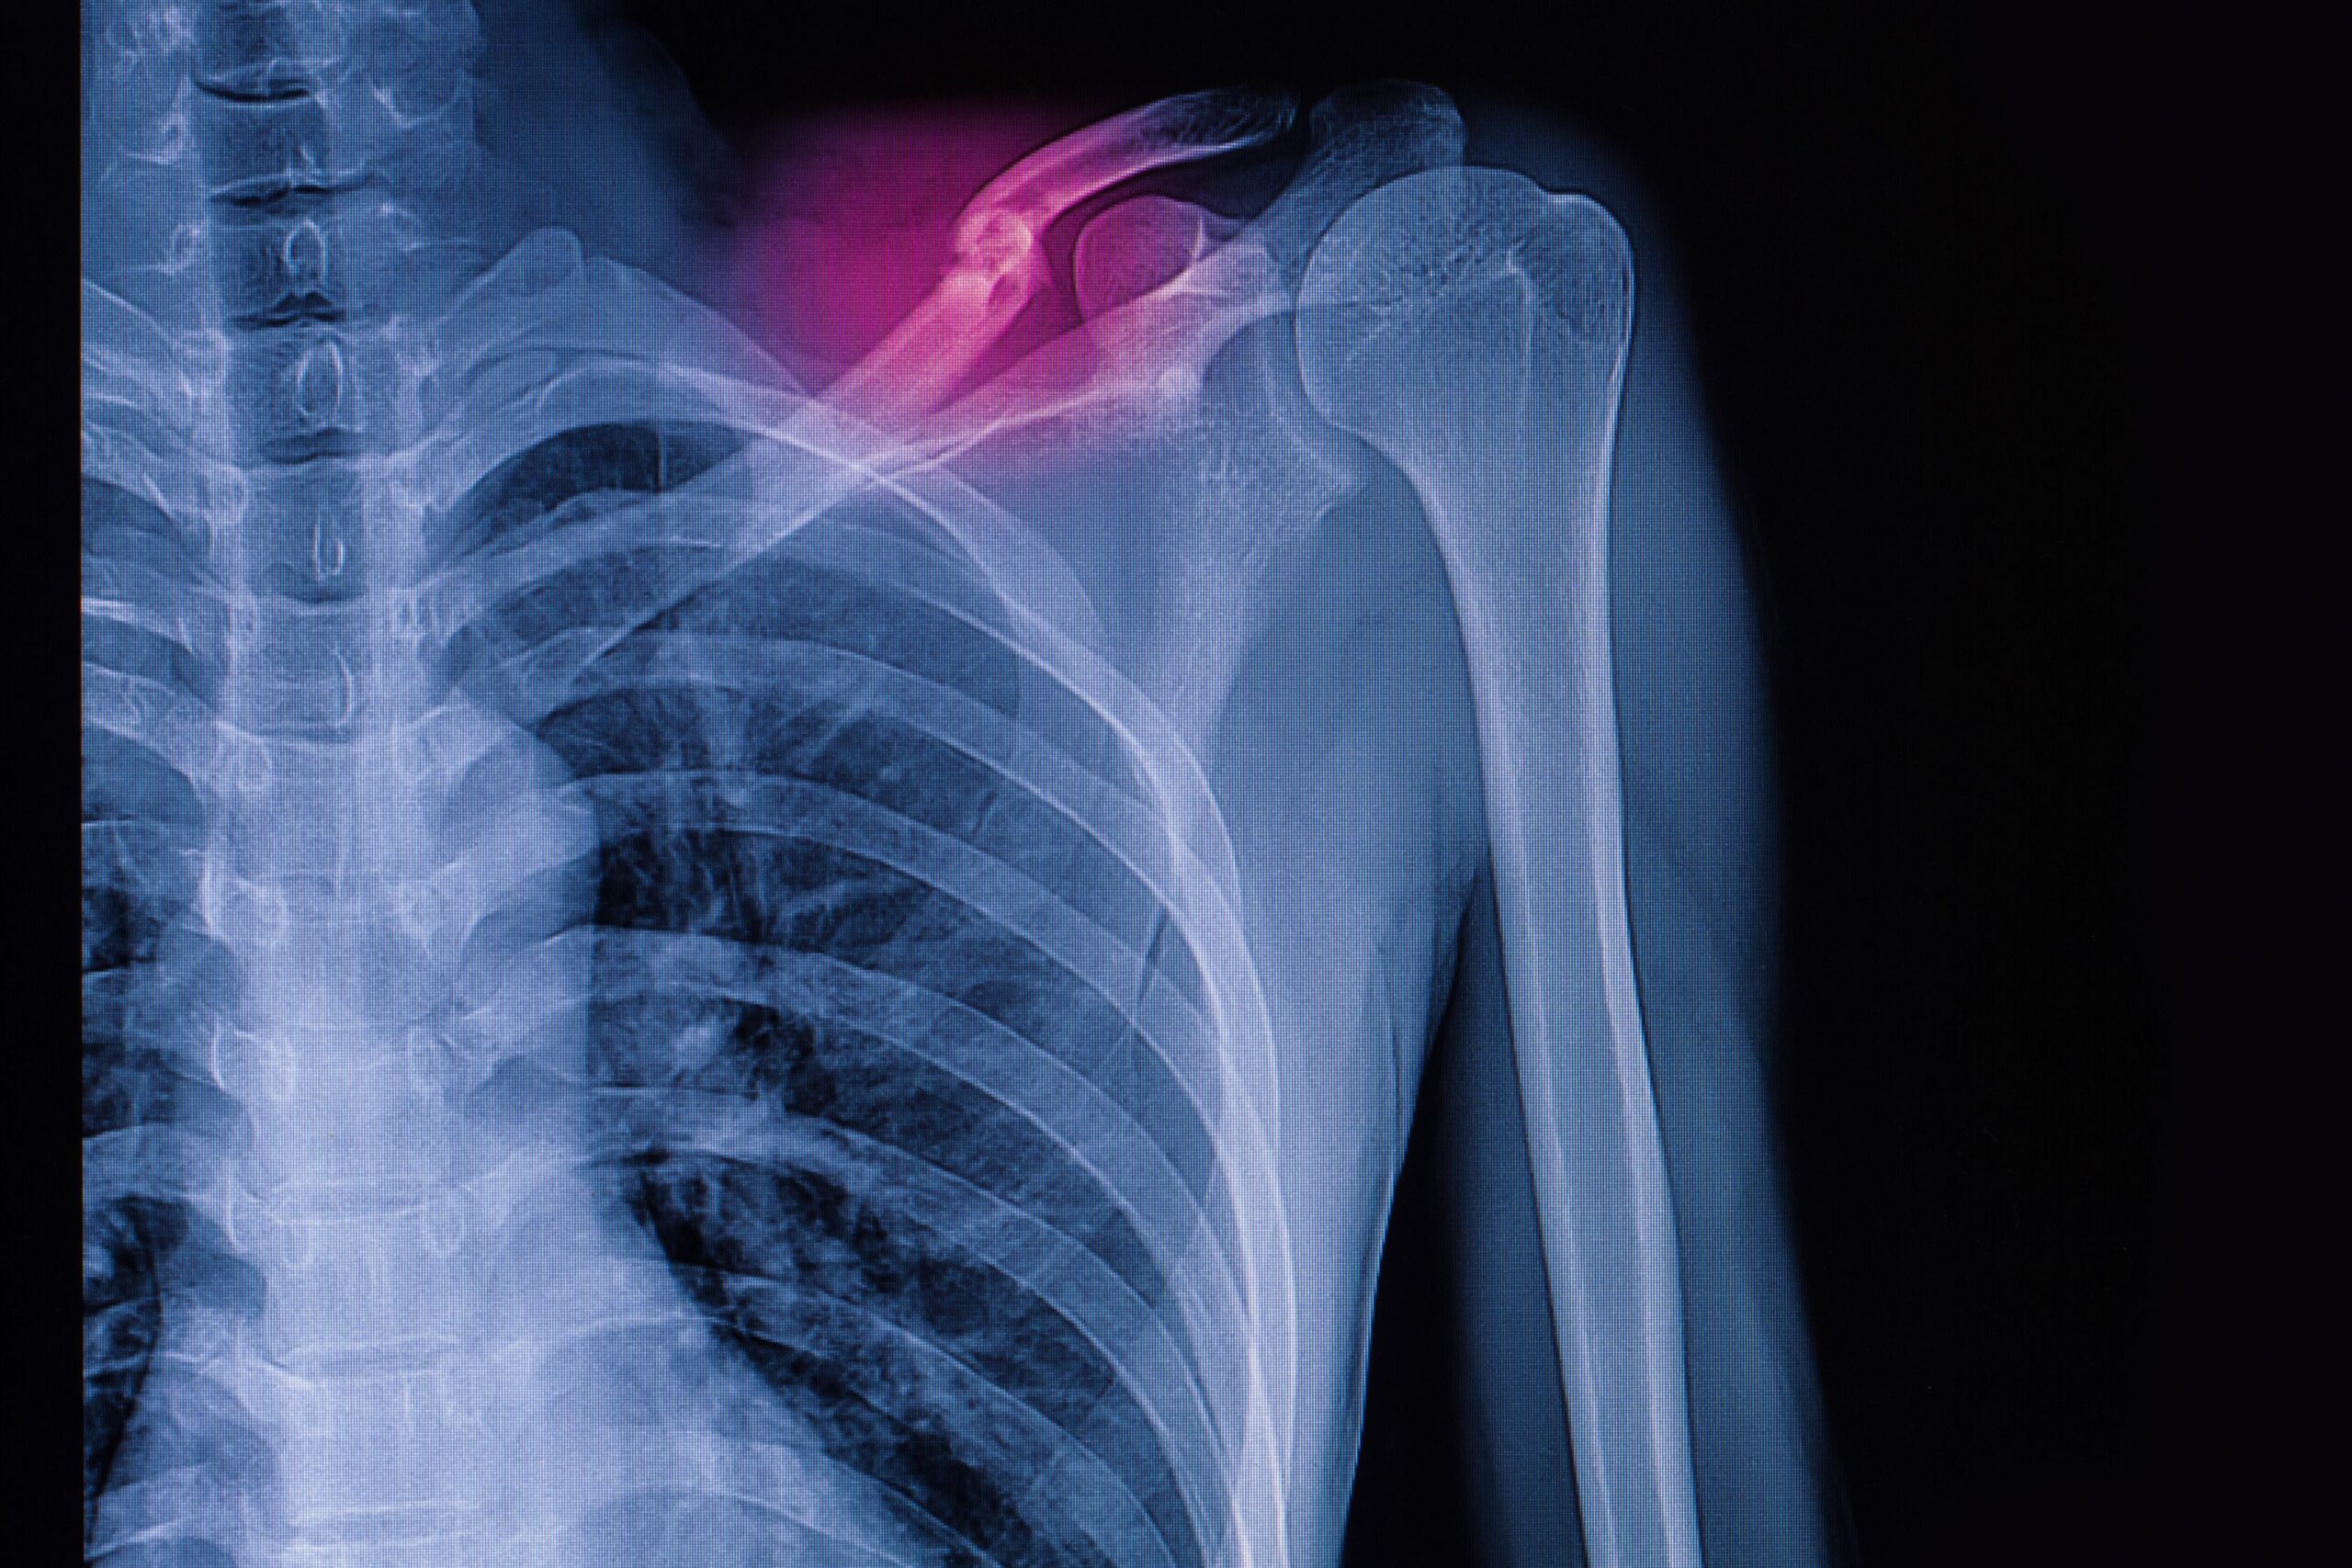

Circa l’80% delle fratture di calvicola avviene a carico del terzo medio, determinando dolore, gonfiore e impotenza nell’usare il braccio corrispondente. Trattata nella maggioranza dei casi per via conservativa in modo ottimale, questa frattura può presentare delle sfide significative, soprattutto se scomposta. In questo caso il trattamento conservativo si associa a un tasso di non unione compreso tra il 7% e il 15%, oltre che a un rischio di sviluppare pseudoartrosi del 15%-20%.

Frattura di clavicola: la fissazione mostra gli esiti migliori